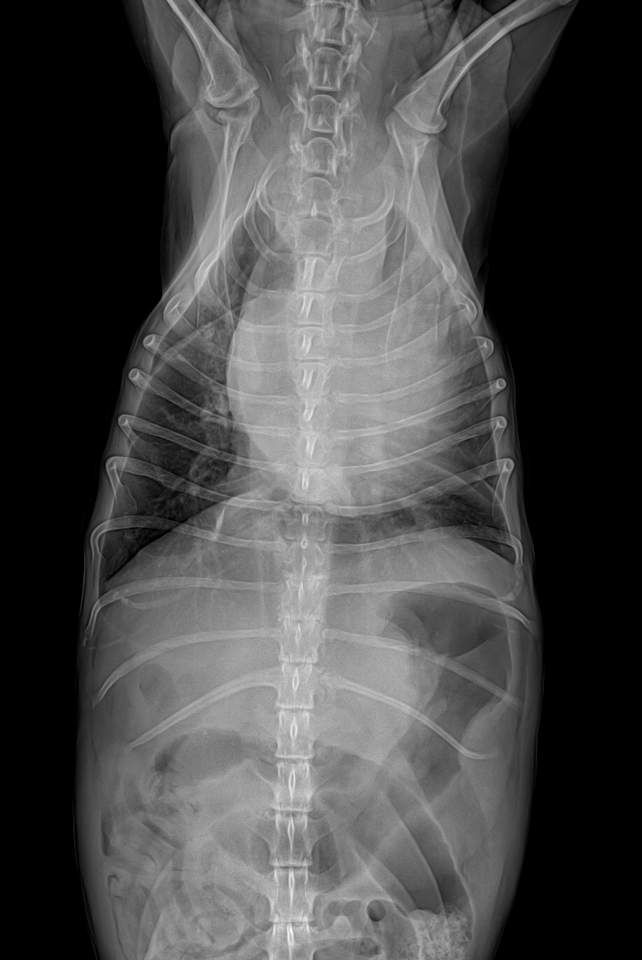

심장도 키기가 매우 크고, 좌심방 돌출이 있으며, 경미하지만 폐수종이 발생한 상태면서, 흉수도 보입니다.

또한 간의 크기가 큰데, 종괴 양상이 보여 간암 가능성이 매우 높아 보이니 복부 초음파 검사와 심장 초음파 검사 모두 필요합니다.